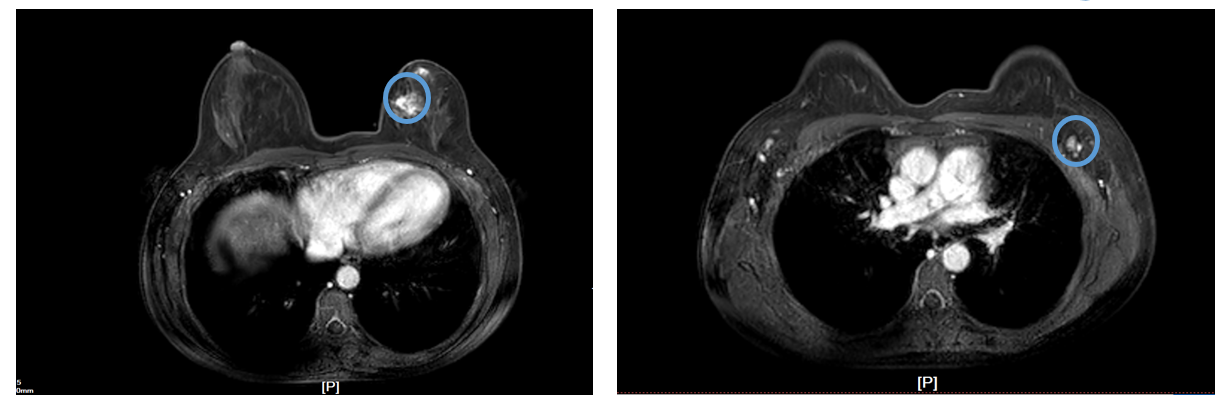

核磁共振检查:左乳内上象限可见大小约2.4cm*3.2cm*2.9cm的肿块影,外形不规则,边缘毛刺,呈稍长T1、长T2信号,DWI相呈稍高信号,增强后病灶明显强化,强化曲线呈流出型,其内前方可见直径约1.5cm的强化结节影。腋窝淋巴结:左腋窝可见轻度肿大淋巴结,较大者长径约1.1cm。诊断:左乳占位,结合病史考虑乳腺癌(BI-RADS 6类),左侧腋窝淋巴结转移可能,局部皮肤受累可能。

核磁共振检查(2021.9.14-2021.12.13)结果提示,左乳内下象限占位,较前范围缩小,左腋窝多发肿大淋巴结,较前缩小。